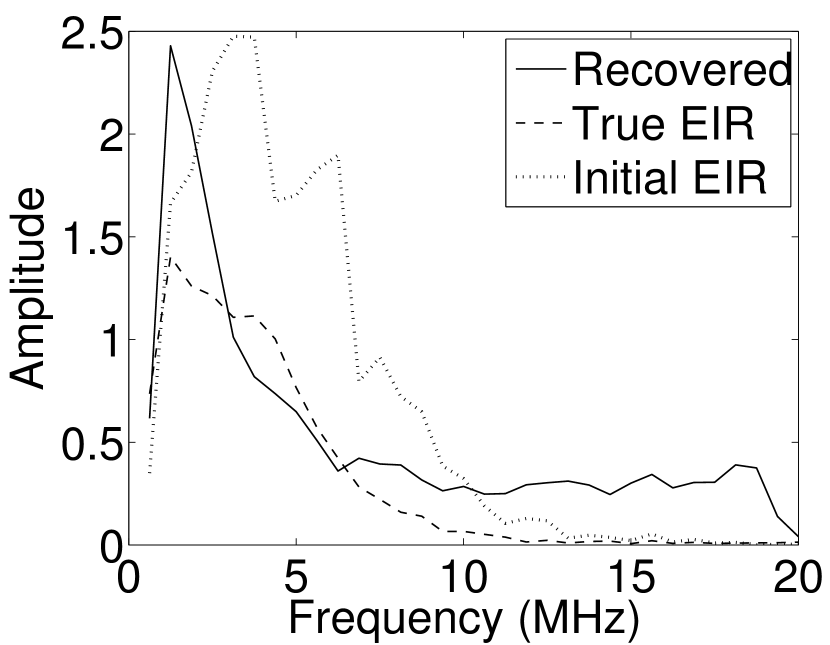

As shown in Figure 6, when the error in the EIR was small (e.g., as with the EIR in Figure 6(a)), images were reconstructed with high accuracy using the VP algorithm. When the perturbations in the EIR were stronger (e.g, as in Figure 6(c)), artifacts and distortions in the reconstructed images were still significantly reduced by use of the VP algorithm; however, larger values of the regularization parameters had to be applied. When as in the initial EIR in Figure 6(e), no improvement was observed in the image reconstructed by use of the VP algorithm.

Images reconstructed by use of the VP algorithm with different values of the regularization parameter values are shown in Figure 8. The recovered EIRs and their corresponding Fourier spectra are shown in Figures 9 and 10, respectively. The RMSE values are computed and displayed together with the corresponding images. As expected, the images reconstructed with smaller values of contain higher noise levels, while images using larger possess a reduced noise level. However, larger values of also caused artifacts in the reconstructed images. The same observation can be made for the effect of the regularization parameter on the recovered EIR. One also observes that the reconstructed images and EIRs depend continuously on the regularization parameters and , i.e. small changes in the regularization parameters cause minor changes in the reconstructed images and EIRs.